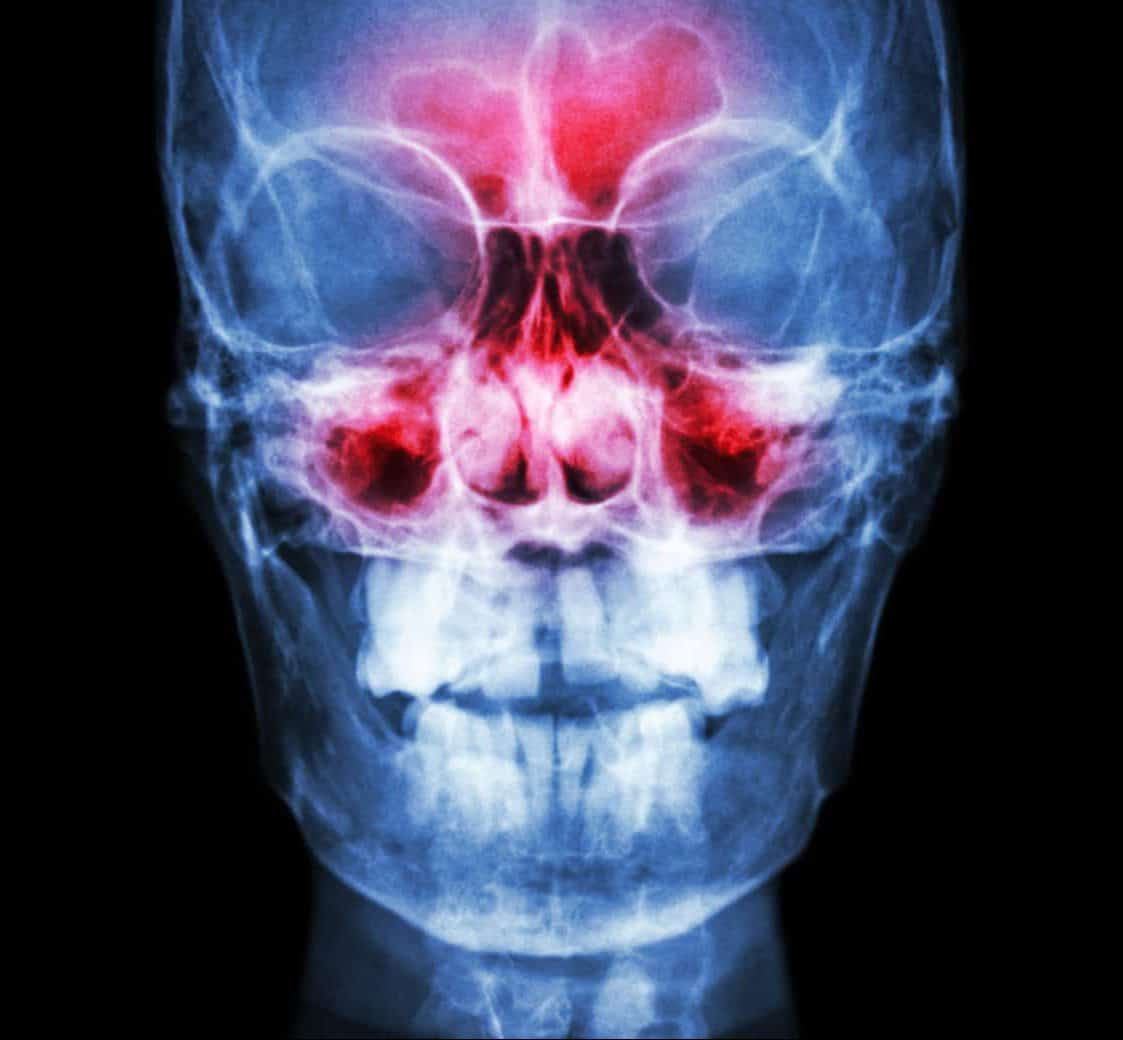

In addition to a physical examination and a review of your medical history, your doctor will inspect your nasal passages for polyps and other abnormalities and check for inflammation and a buildup of fluid. Additional tests utilizing nasal endoscopy, CT scans, MRIs and allergy tests can be used to help confirm the diagnosis.